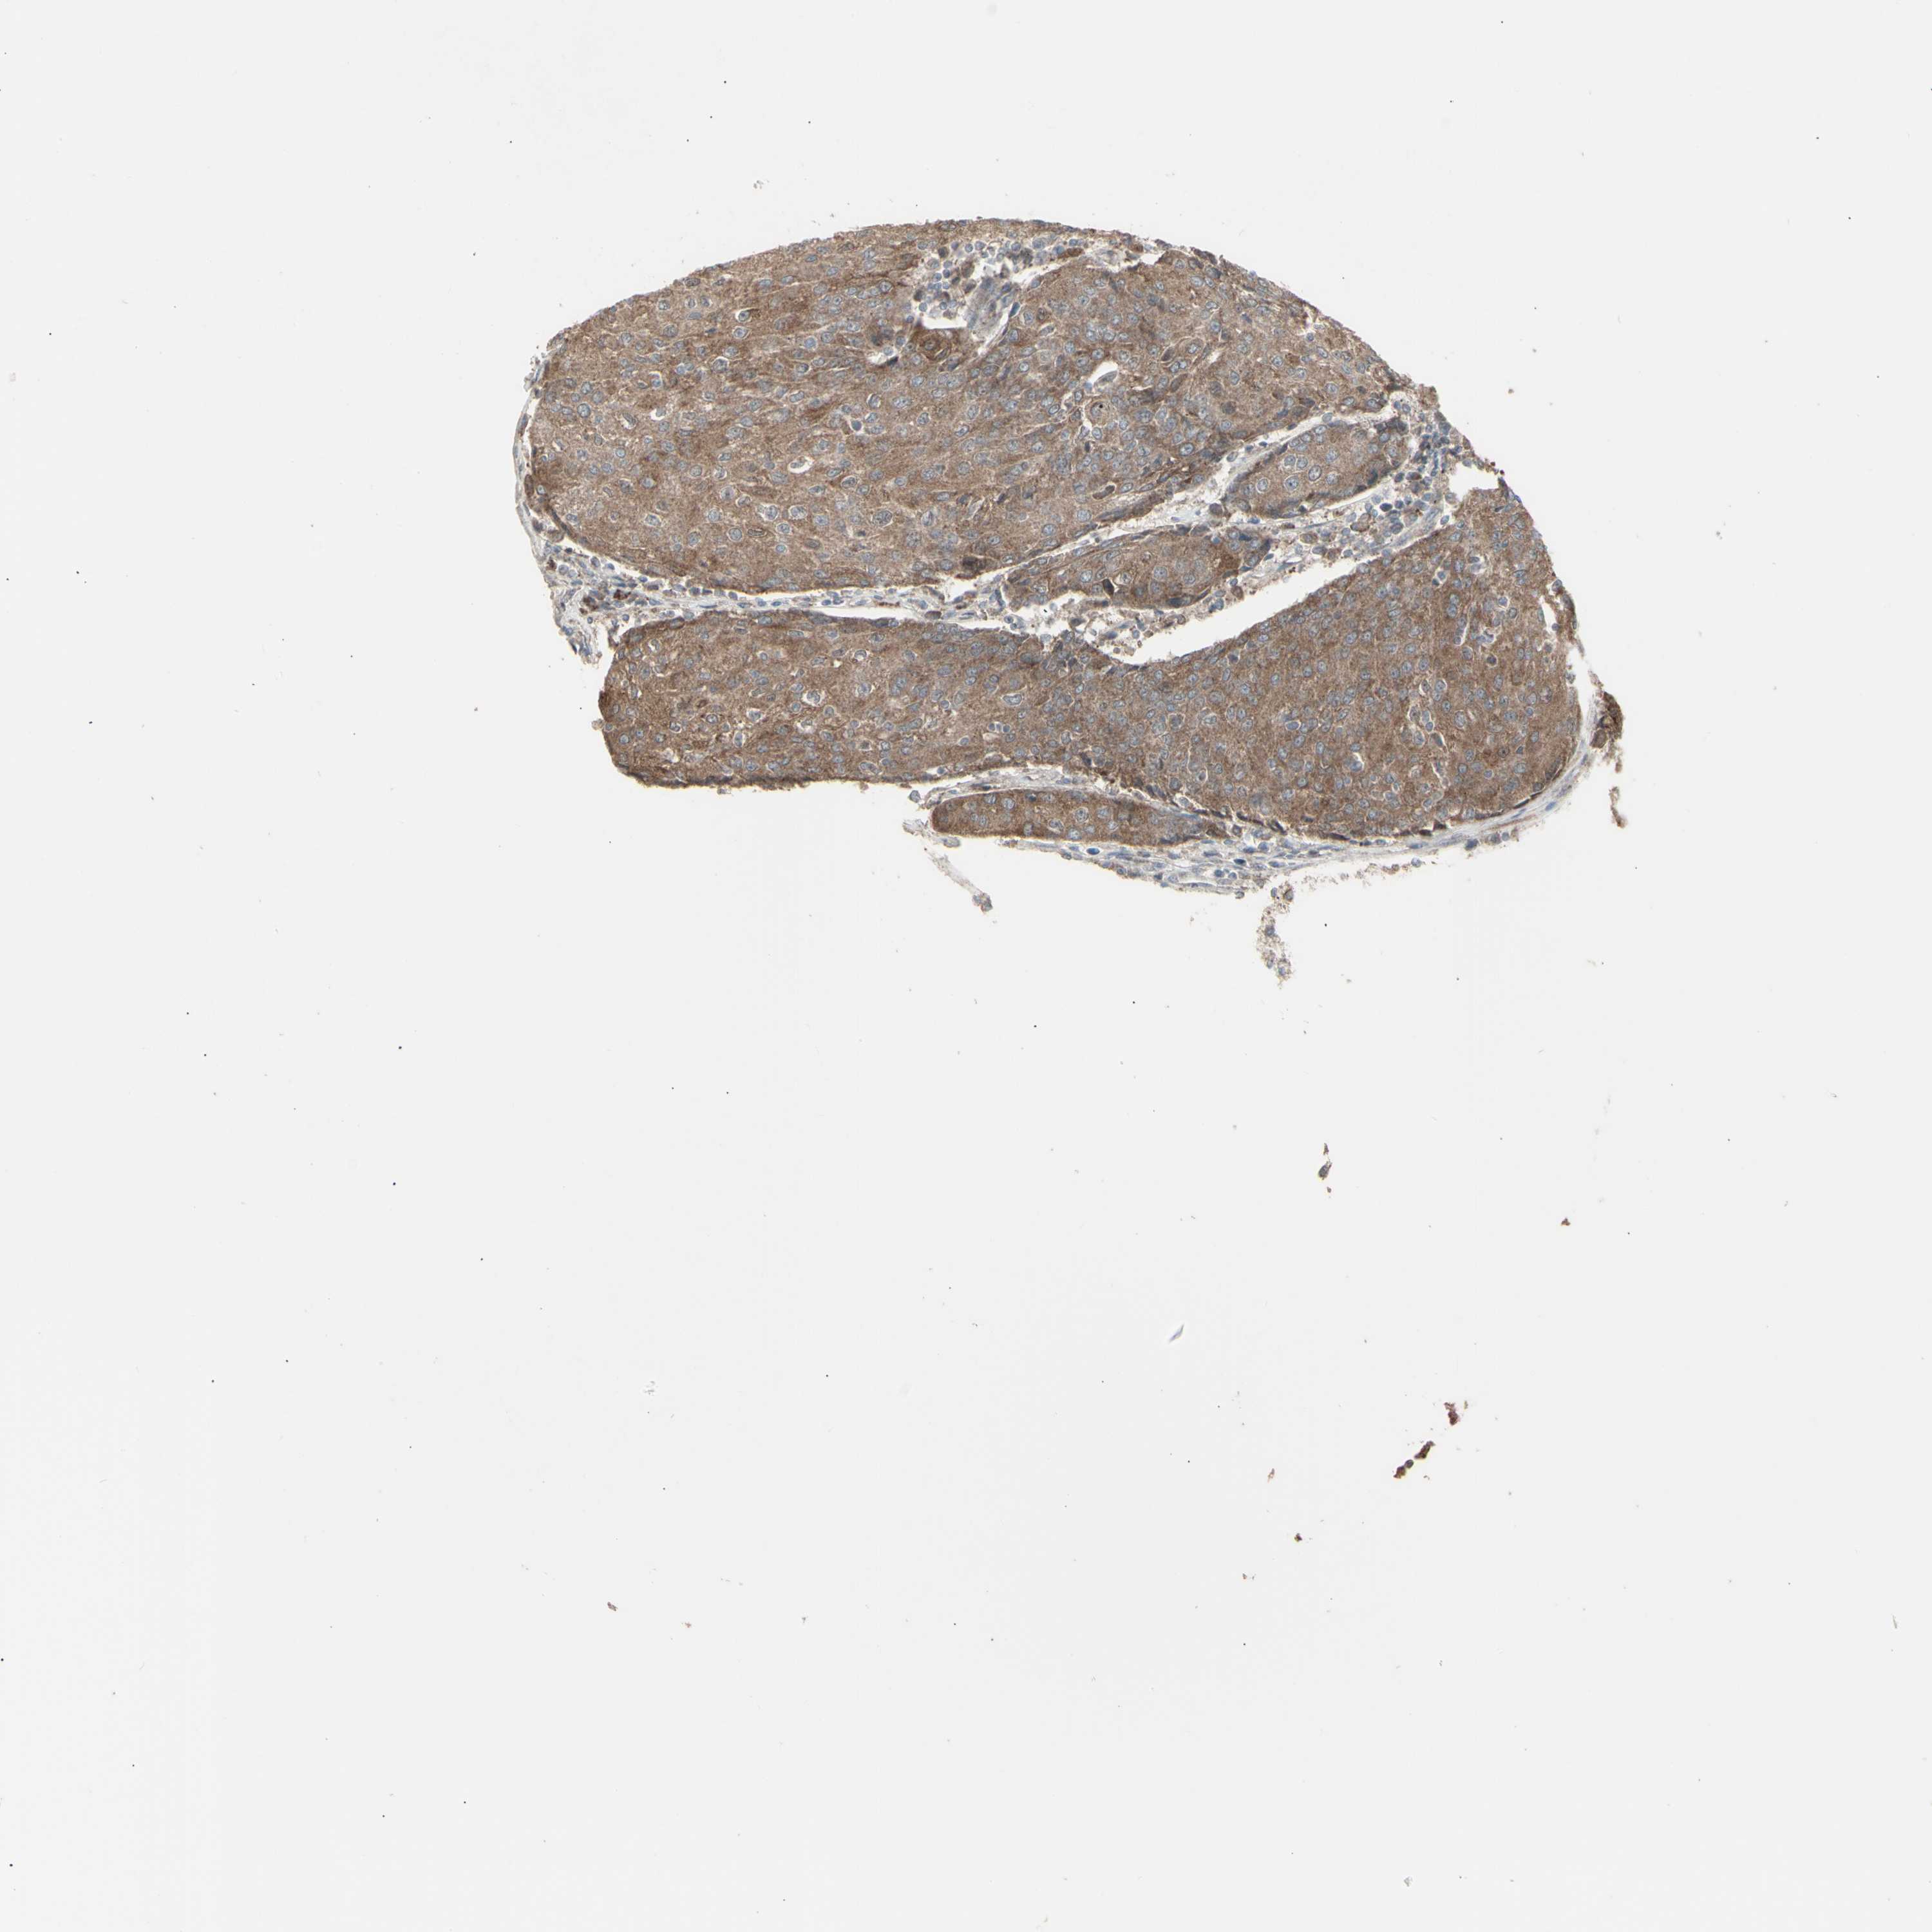

UROTHELIAL CANCER - Protein expressioni

A mouse-over function shows sample information and annotation data. Click on an image to view it in a full screen mode. Samples can be filtered based on level of antibody staining by selecting one or several of the following categories: high, medium, low and not detected. The assay and annotation is described here.

Antibody stainingi

Antibody staining in the annotated cell types in the current human tissue is reported as not detected, low, medium, or high, based on conventional immunohistochemistry profiling in selected tissues. This score is based on the combination of the staining intensity and fraction of stained cells.

Each image is clickable and will lead to virtual microscopy that enables deeper exploration of all samples and also displays staining intensity scores, fraction scores and subcellular localization as well as patient and tissue information for each sample.

Antibody HPA002633

Antibody HPA046758

Antibody CAB010906

Staining

High

Medium

Low

Not detected

Intensity

Strong

Moderate

Weak

Negative

Quantity

>75%

75%-25%

<25%

None

Location

Nuclear

Cytoplasmic/membranous

Cytoplasmic/membranous,nuclear

Urothelial carcinoma, High grade

Urothelial carcinoma, Low grade